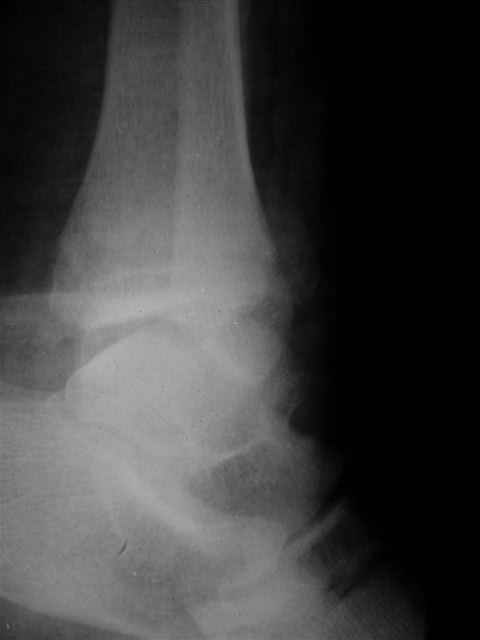

> интересуюсь тактикой лечения повреждений голеностопного сустава.

Я предупреждал, что ничего сверхъестественного. Каюсь, что одна из спиц прошла несколько дальше, чем нужно было, но главное - перелом стабилизирован и больной работает суставом в полном объёме, несмотря на представленную раннее травму коленного сустава.